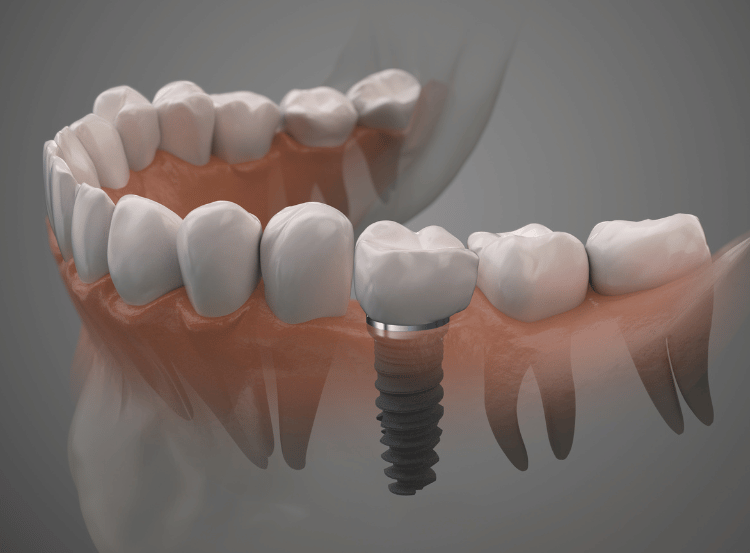

Unlike removable options, single tooth implants are fixed into the jaw and designed to last many years. They provide a stable foundation so there’s no slipping or movement.

By replacing the missing tooth root, implants help maintain bone density and prevent neighbouring teeth from shifting. Unlike traditional bridges, they do not require drilling into healthy teeth.

The ceramic crown is custom-made to match the shape, size, and shade of your natural teeth. The implant functions like a real tooth, allowing you to eat, chew, and speak with confidence, and it can be maintained with regular brushing, flossing, and dental check-ups.

The titanium implant is carefully placed into the jaw under local anaesthetic. If the natural tooth is still present, it will be extracted first. For nervous patients, sedation can also be provided.

Once healed, an impression is taken to design a bespoke crown that blends seamlessly with your smile. The crown is then securely attached to the implant, restoring your bite and appearance. From start to finish, treatment usually takes around six to eight months, depending on healing time.